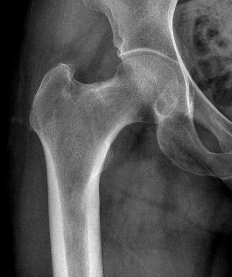

CT

Fracture line

CT demonstrating incomplete fracture at inferior neck

CT demonstrate likely complete fracture, with some displacement